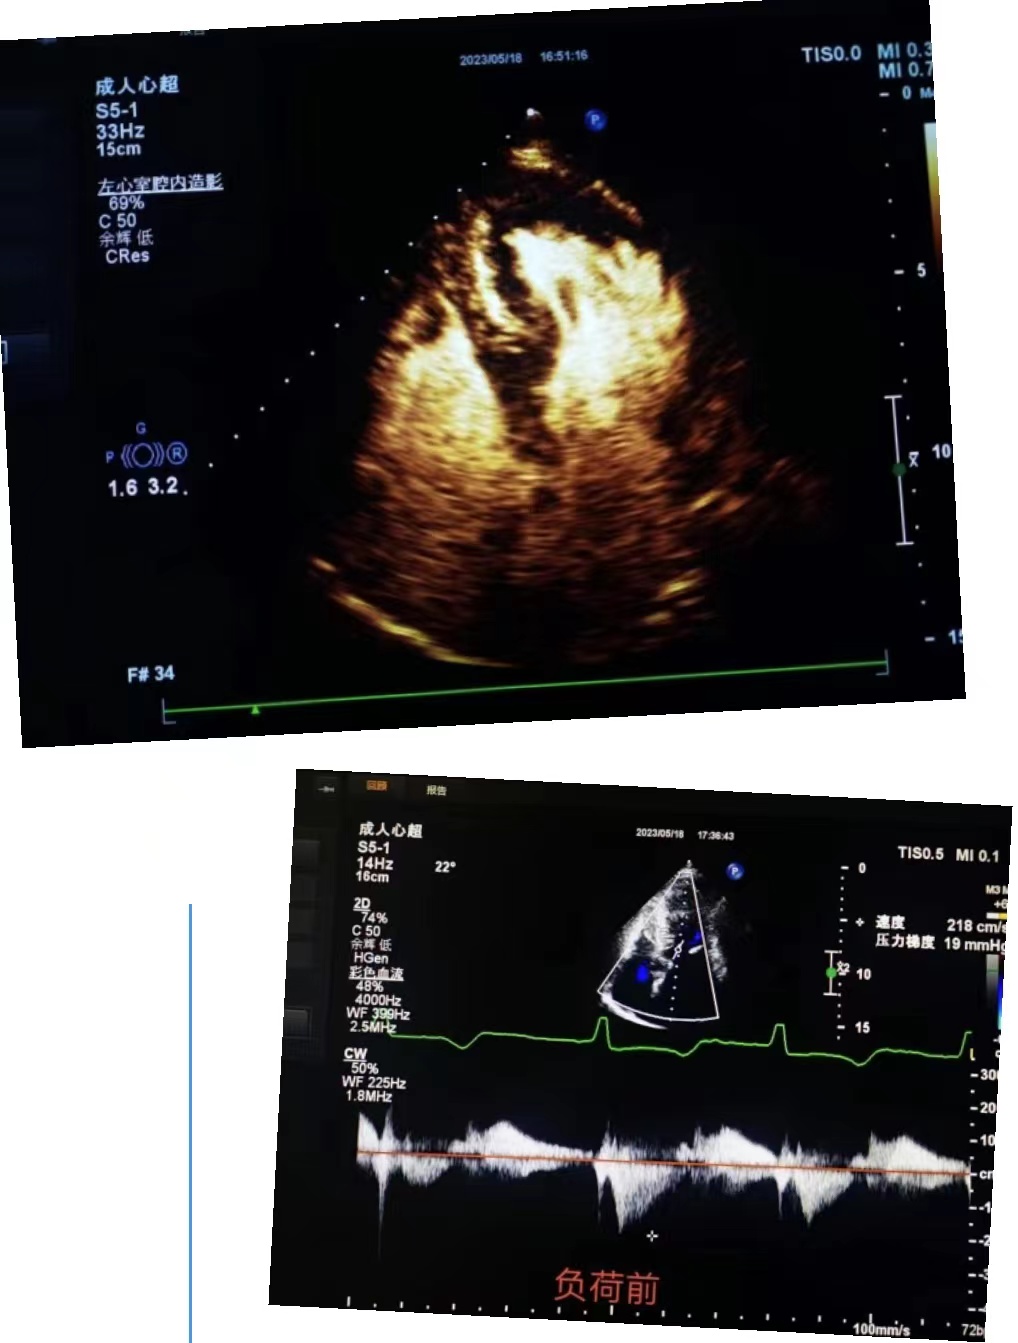

超聲科王英莉主任及心血管組賈貝主治醫(yī)師、陳輝主管護(hù)師及牛丹青護(hù)師為該患者行藥物負(fù)荷超聲心動(dòng)圖。監(jiān)護(hù)儀、急救車到位,常規(guī)經(jīng)胸超聲心動(dòng)圖提示室間隔增厚,左室流出道血流速度略增快,左心腔超聲造影,可清晰顯示室壁顯著增厚,符合肥厚型心肌病表現(xiàn),隨后又進(jìn)行了多巴酚丁胺負(fù)荷超聲心動(dòng)圖,靜息狀態(tài)下顯示左室流出道血流速度V:207cm/s,PG:17mmHg;3分鐘后心率達(dá)75次/分,左室流出道血流速度V:218cm/s,PG:19mmHg;6分鐘后心率達(dá)94次/分,左室流出道血流速度V:386cm/s,PG:60mmHg;9分鐘后達(dá)到目標(biāo)心率,左室流出道血流速度V:649cm/s,PG:169mmHg,停止用藥,藥物負(fù)荷試驗(yàn)陽性,檢查過程中患者無不適癥狀,最終診斷為隱匿性肥厚型梗阻性心肌病。